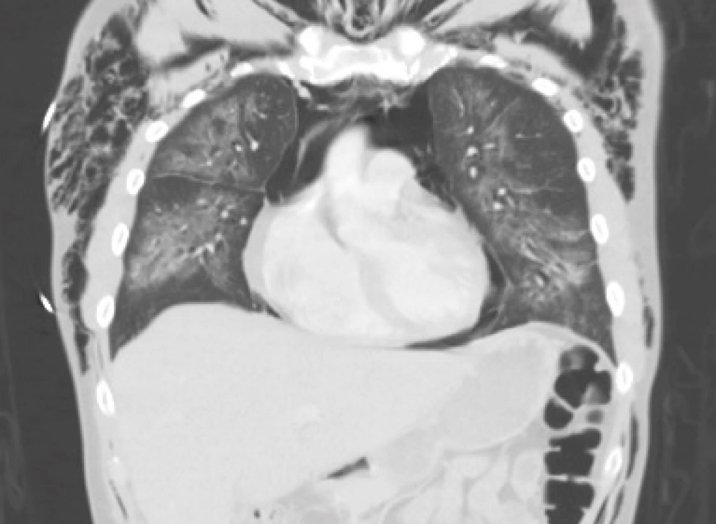

Electronic cigarette (e-cigarette) or vaping associated lung injury (EVALI) cases have increased with the popularity of e-cigarettes in the mostly young, healthy population. Some common symptoms associated with EVALI include shortness of breath and chest pain, and the most common diagnostic imaging findings are organizing pneumonia and diffuse alveolar damage seen on computed tomography (CT). Pneumomediastinum is a known sequela of EVALI.1 In the setting of pneumomediastinum in EVALI, EVALI is a diagnosis of exclusion, so other sources of pneumomediastinum need to be evaluated. EVALI has diverse presentations, and this case is a unique representation of a disease process that is becoming more commonplace with the increase in popularity of vaping. It is important to be aware of the clinical symptoms of EVALI, which can be nonspecific and can include gastrointestinal symptoms along with respiratory symptoms. It is equally important to recognize the diverse image findings of EVALI, which can include subcutaneous emphysema and pneumomediastinum. In this case, pneumomediastinum is seen in EVALI, and the patient was successfully treated with empiric antibiotic coverage, steroids, and conservative measures—making sure to limit any coughing or increases in intrathoracic pressure that can cause worsening of pneumomediastinum.